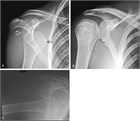

脱臼した上腕骨頭により三角胸筋溝は膨隆し,上腕骨頭に本来あるはずの肩峰下が空になり,肩峰は外側に突出しているようにみえる(128.1).

肩関節脱臼のうち,90~98%は上述のような前方脱臼である.その他の大部分は後方脱臼であり,通常は外傷(症例の67%),てんかん発作(同31%),高電圧の電撃(同2%)によって引き起こされる.患者は肩関節痛のみを訴え,腕を内旋・内転させ抱えて来院する.後方脱臼はAP像(Anterior- Posterior view)やスカプラY撮影ではわかりにくいことがある.上腕骨頭の内旋位(いわゆる“light- bulb sign”)が唯一の徴候である場合がある.もしAP像やスカプラY撮影の読影が難しく臨床判断がつきかねる場合は,軸位撮影(Axillary view)を行うべきである(図128.2).